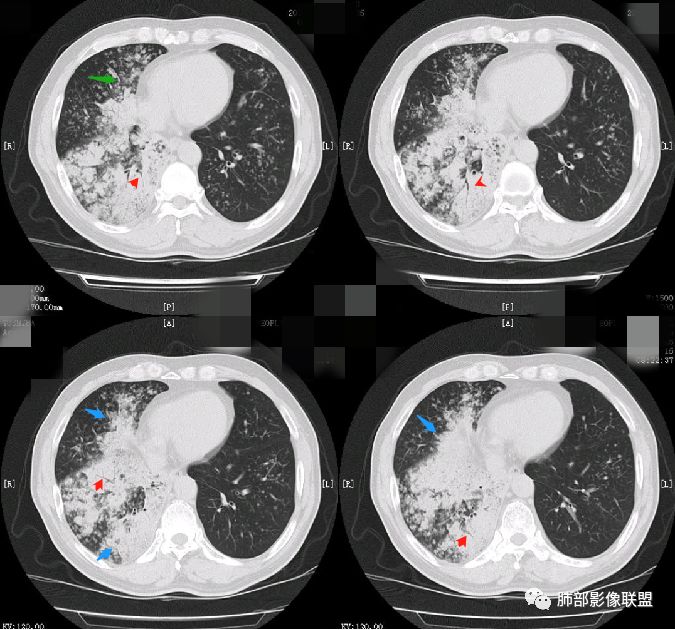

病灶内支气管情况如何?

支气管走形僵直、狭窄、中断,分支减少,呈“枯树枝”改变(图1-4红色短箭头)。可惜没有增强,不能了解病灶强化及血管情况。

周围肺野情况如何?

周围肺野有边界清楚GGO,局部中轴间质明显增厚并呈结节样改变(图1绿色箭头),树芽征不明显